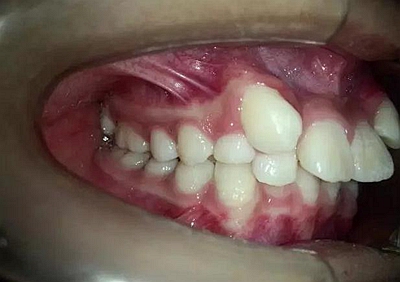

14歲,牙齒嚴(yán)重?fù)頂D,上頜兩個(gè)尖牙在側(cè)切牙唇側(cè)

采用細(xì)絲排齊,8字結(jié)扎控制尖牙,此時(shí)如果直接拉尖牙,勢(shì)必導(dǎo)致上頜磨牙近中移動(dòng),更何況磨牙本來就是遠(yuǎn)中關(guān)系,需要強(qiáng)支抗。

幾個(gè)月后,換上不銹鋼方絲,側(cè)切牙遠(yuǎn)中彎制了一個(gè)內(nèi)展彎,避免了尖牙遠(yuǎn)中移動(dòng)時(shí)與弓絲形成頜干擾。

兩個(gè)月后效果還是比較明顯的。